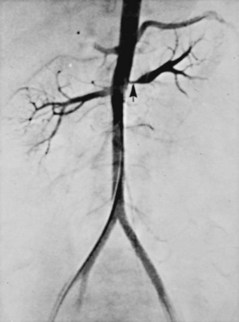

Angiographically, medial fibroplasia demonstrates a typical “string of beads” appearance involving the distal two thirds of the main renal artery and branches (Fig. 39–4). The areas of stenosis are often overshadowed by contrast medium in the microaneurysms, making the degree of actual stenosis difficult to assess. The aneurysms themselves are greater in diameter than the normal renal artery proximal to the disease, and extreme collateral circulation is absent. These are important features in differentiating the lesion from perimedial fibroplasia. Schreiber and colleagues (1984) studied the natural history of renal artery disease due to medial fibroplasia in 66 patients who were followed with serial angiography. Progressive renal artery stenosis (RAS) occurred in 22 patients (33%), and, contrary to an earlier report, this occurrence was no different whether patients were older or younger than 40 years. Significantly, there were no cases of progression to total arterial occlusion in this group. Also, clinical follow-up revealed that serial decreases in either overall renal function or the size of the involved kidney seldom occurred in patients with progressive medial fibroplasia, suggesting that the risk of losing renal function is relatively small in patients with this disease who are managed medically.

Figure 39–4 Selective right renal arteriogram reveals medial fibroplasia involving the main renal artery with typical “string of beads” appearance.

(From Novick AC. Renal vascular hypertension in children. In: Kelalis PP, King LR, Belman AB, editors. Clinical pediatric urology. Philadelphia: WB Saunders; 1984.)